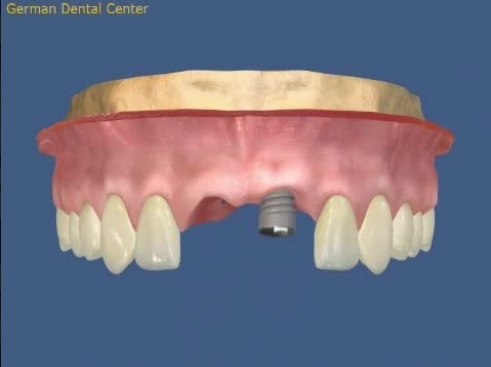

- Имплантация

- Протезирование